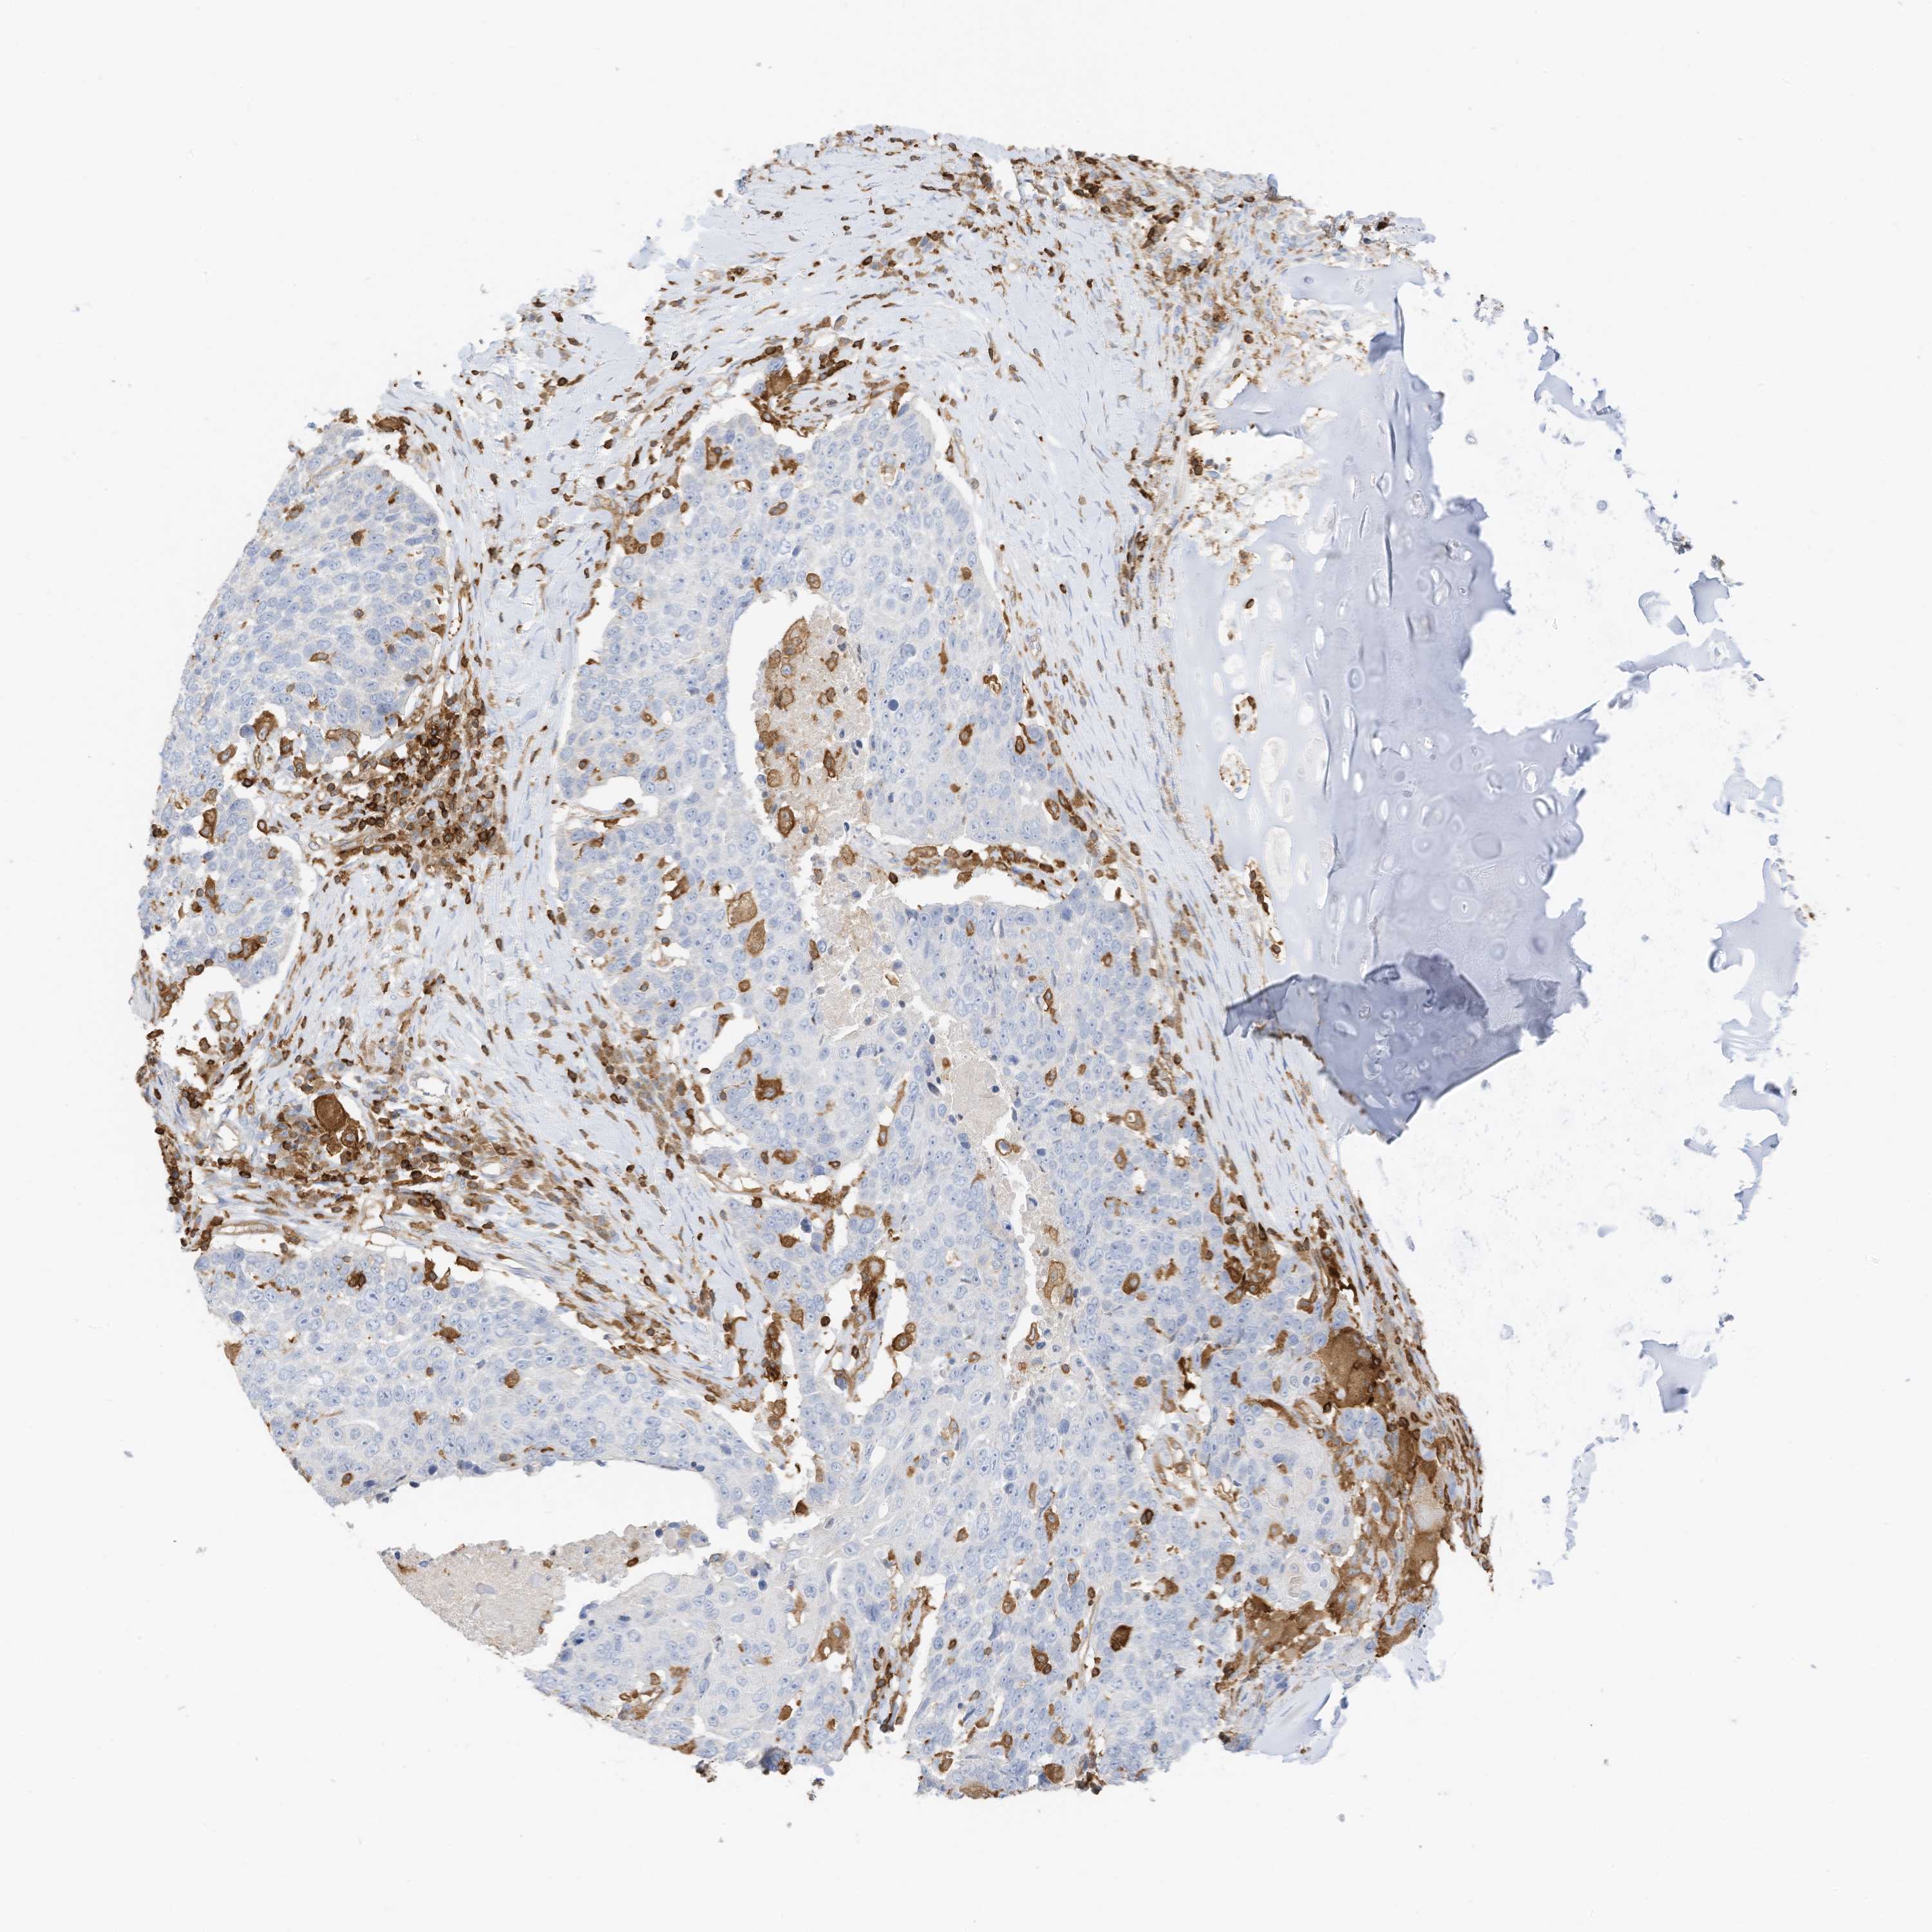

LUNG ADENOCARCINOMA (VALIDATION) - Interactive survival scatter ploti

The Survival Scatter plot shows the clinical status (i.e. dead or alive) for all individuals in the patient cohort, based on the same data that underlies the corresponding Kaplan-Meier plots. Patients that are alive at last time for follow-up are shown in blue and patients who have died during the study are shown in red.

The x-axis shows the expression levels (FPKM) of the investigated gene in the tumor tissue at the time of diagnosis. The y-axis shows the follow-up time after diagnosis (years). Both axes are complimented with kernel density curves demonstrating the data density over the axes. The top density plot shows the expression levels (FPKM) distribution among dead (red) and alive patients (blue). The right density plot shows the data density of the survived years of dead patients with high and low expression levels respectively, stratified using the cutoff indicated by the vertical dashed line through the Survival Scatter plot. This cutoff is automatically defined based on the FPKM cutoff that minimizes the p-score. The cutoff can be changed by dragging the vertical line or by entering a cutoff value in the square labeled "Current cut-off".

Under the Survival Scatter plot the p-score landscape (black curve; left axis) is shown together with dead median separation (red curve; right axis). Dead median separation is the difference in median mRNA expression between patients who have died with high and low expression, respectively. It is calculated as follows: median FPKM expression of dead patients with high expression - median FPKM expression of dead patients with low expression. This is intended to aid the user in visually exploring custom cutoffs and the associated p-scores and dead median separation.

Individual patient data is displayed and can be filtered by clicking on one or more of the category buttons on the top of the page. Categories describing expression level and patient information include: high, low, alive, dead, female, male and tumor stages. The scale of the x-axis can be toggled between linear and log-scale by clicking on the "x log" button. Mouse-over function shows TCGA ID, patient information and mRNA expression (FPKM) for each patient.

& Survival analysisi

Kaplan-Meier plots summarize results from analysis of correlation between mRNA expression level and patient survival. Patients were divided based on level of expression into one of the two groups "low" (under cut off) or "high" (over cut off). X-axis shows time for survival (years) and y-axis shows the probability of survival, where 1.0 corresponds to 100 percent.

ARHGAP25 is not prognostic in Lung Adenocarcinoma (validation)

Best expression cut offi

: 13.45

Average pTPM 21.0

Number of samples 105